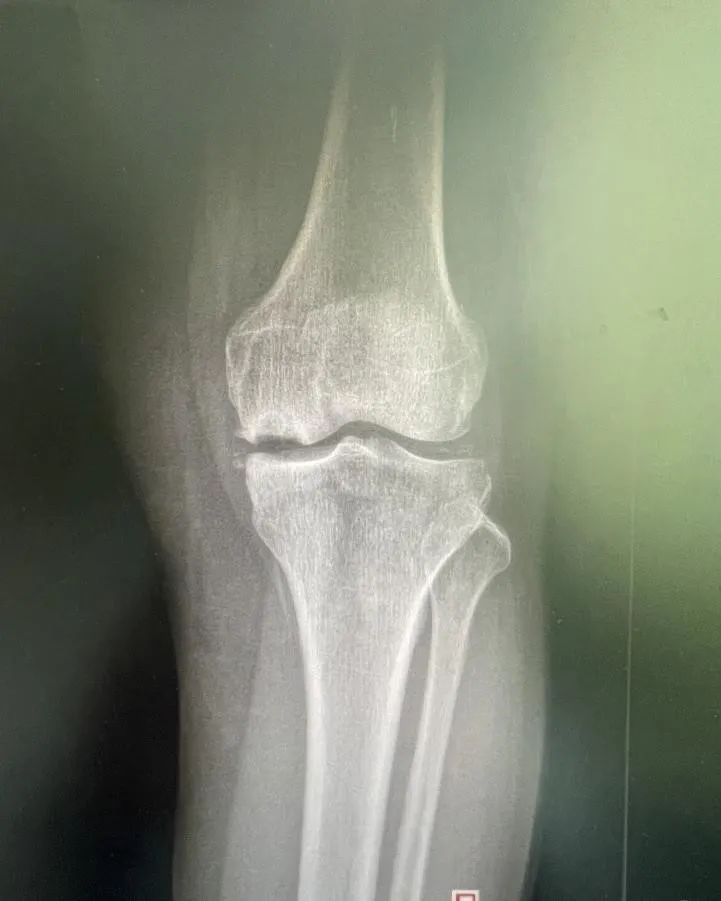

膝关节疼痛背后的真相 术前检查片 老年膝关节疼痛通常被认为是由于骨头磨损所致,但实际情况可能更为复杂。例如,73岁的梁大姐就经历了这种痛苦。她的症状包括走路困难、关节肿胀和持续的疼痛。经过详细的检查和诊断,医生发现梁大姐患有膝关节内侧自发性骨坏死,这是一种不常见的疾病。这种病症涉及到软骨的退变、软骨下骨的水肿以及骨头的坏死,这些因素共同导致了剧烈的疼痛。 单髁置换术——治疗新选择 针对梁大姐的情况,ky骨科一区的许国胜主任提出了三种手术方法:关节镜手术、全膝关节置换术和单髁置换术。考虑到创伤大小、术后恢复速度和功能恢复等因素,最终选择了单髁置换术。这种手术仅更换受坏死影响的内侧间室骨头,同时保留了外侧间室、髌股关节和交叉韧带的正常功能。与传统全膝关节置换相比,单髁置换具有创伤小、疼痛轻、恢复快等优点。 术后效果与快速康复 梁大姐在接受了内侧单髁置换术后,第二天就能下地走路,并在术后第三天出院回家。一个月后复查时,她的左膝关节内侧疼痛症状完全消失,关节活动自如。这一案例证明了单髁置换术的有效性。此外,该手术在国外已有超过30年的历史,在国内外也有超过15年的应用时间,技术成熟且效果稳定可靠。对于早期病变的患者来说,单髁置换术不仅能明显改善生活质量,还能延缓全膝置换的时间。